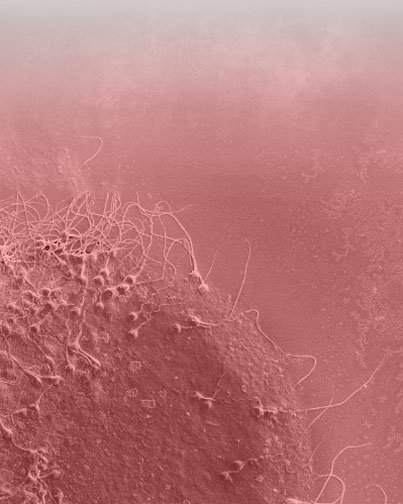

دراسة خصوبة شخصية لتخصيص العلاج